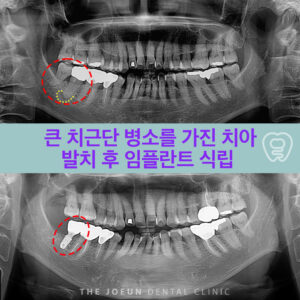

대구성서임플란트 큰 치근단 병소를 가진 치아 발치 후 임플란트 식립

대구성서임플란트 큰 치근단 병소를 가진 치아 발치 후 임플란트 식립   충치나 치주염이 심각한 수준으로 진행되면 발치 후 임플란트 식립을 고려할 수 있지만 자연치에 비해 기능적, 심미적으로 뒤떨어질 수 밖에 없습니다. 따라서 전문적인 보존치료가 선행되어야 하며 이러한 시도가 실패했다면 최후의 보루로 임플란트 식립을 고려하는 것이 바람직한데요. 특히 치아 뿌리에 염증이 더보기…